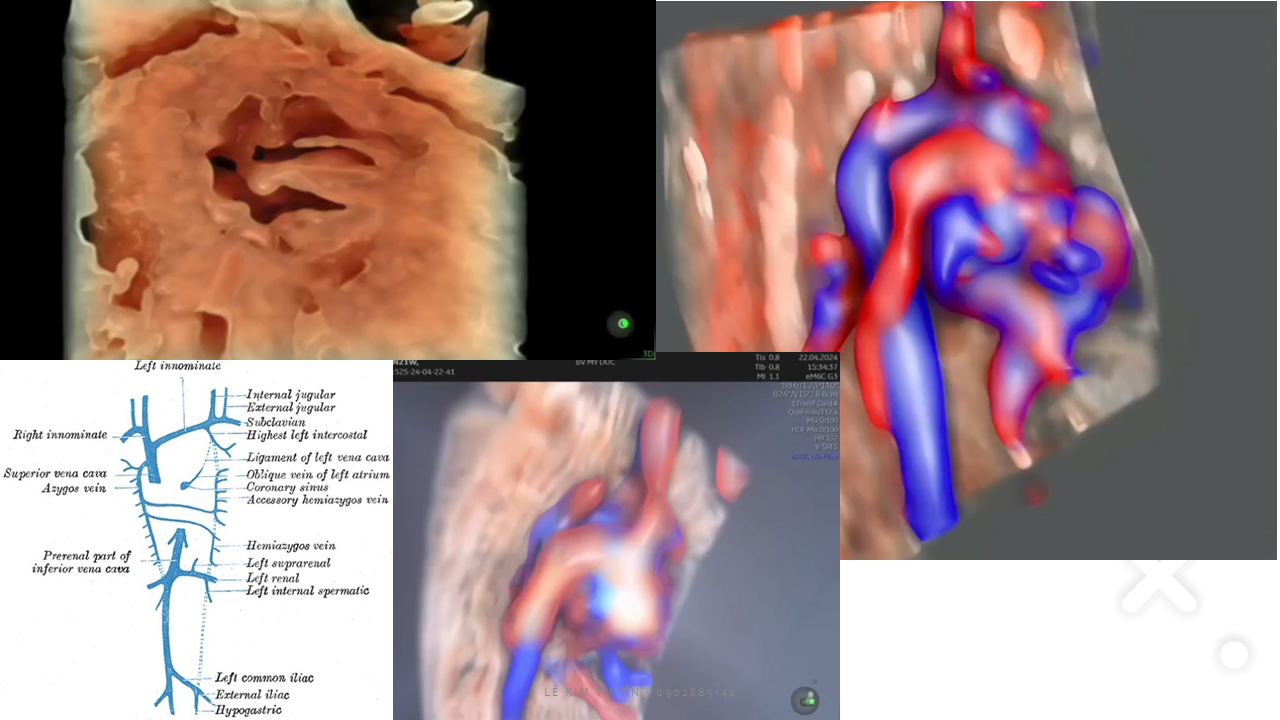

Siêu âm tim thai - Các kỹ thuật hiện đại

TS. BS. Lê Kim Tuyến

Bệnh viện Tim Tâm Đức